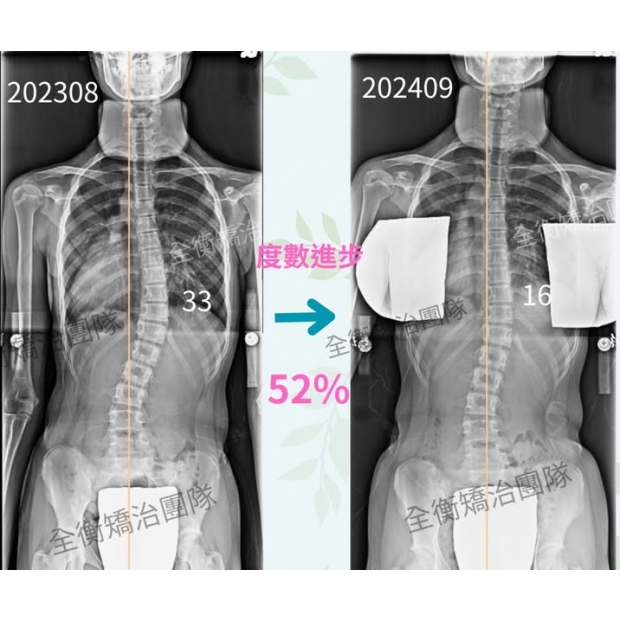

13歲側彎女孩,1年,胸彎從33度進步到16度

女孩在13歲時,家長發現她背部一高一低、體態不對稱,

經過醫師檢查發現女孩有33度的胸彎,

在我們團隊一系列專業側彎矯正運動治療及穿戴施羅斯背架

一年的時間,女孩從原先的33度減少到16度,整整進步52%